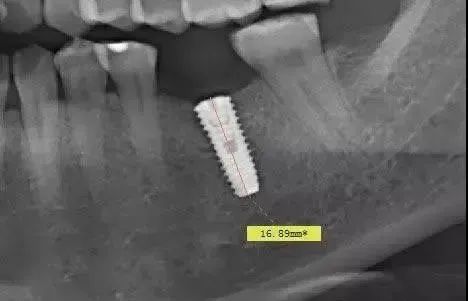

这个种植病例选择了长度为13mm的种植体(OSSTEM系统),种植术后拍摄全景片再次测量我们就会发现,原本13mm的种植体在全景片上被放大至16.89mm,几乎相差4mm。